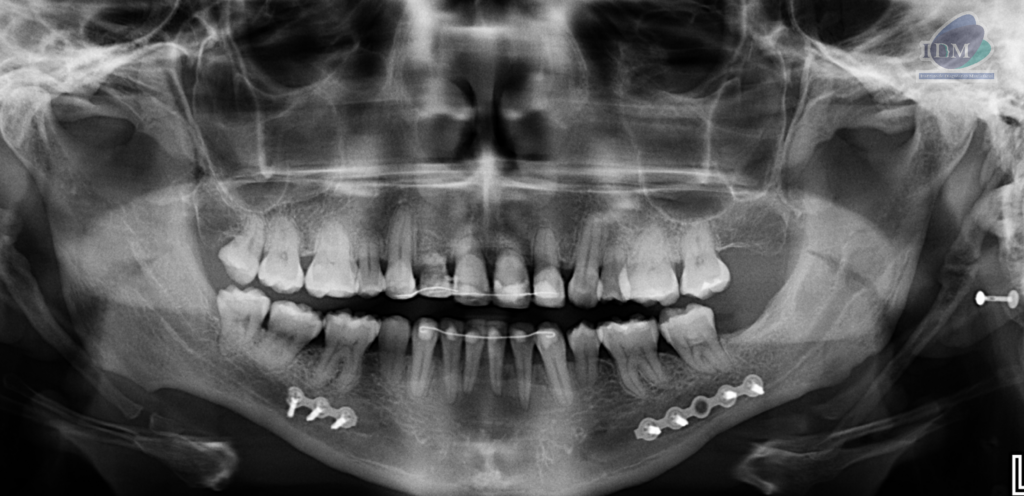

Radiografia Panorámica

A la evaluación de la radiografía panorámica se evidencia una disminución generalizada de la longitud radicular así como la presencia de alambre de fijación en sector dentario anterior y ausencia de algunas piezas dentarias. Siendo lo más resaltante la presencia de un tejido mineralizado en zona cervical de ambos lados, presentando con un patrón lineal pseudoarticulado.

- Mineralización bilateral de la cadena estilohioidea del tipo pseudoarticulada.